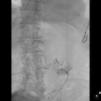

Varón de 78 años ingresado en cuidados intensivos por hematoma subdural con desarrollo de síndrome de distrés respiratorio agudo (SDRA) por neumonía nosocomial y desconexión prolongada de la ventilación mecánica invasiva. Traqueostomizado y precisando gastrostomía percutánea (PG) se inicia ventilación mecánica no invasiva (VMNI) como apoyo en retirada de respirador, desarrollando neumoperitoneo en radiografía de control (fig. 1) de manera asintomática, descartándose perforación de víscera hueca o complicaciones de la PG mediante prueba de imagen con contraste oral (figs. 2 y 3). La VMNI es causa muy infrecuente de neumoperitoneo benigno a tener en cuenta en pacientes ventilados y portadores de gastrostomía. El tratamiento debe ser conservador.